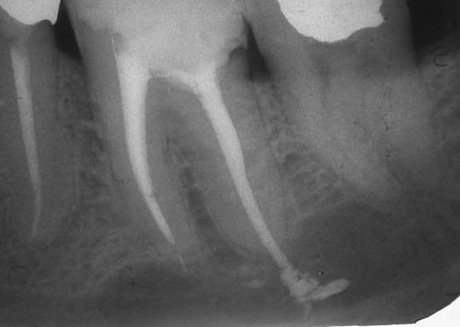

É possível diagnosticar tal complicação somente depois de estudar os dados de raios-X ou visográficos em um computador. Porém, a radiografia panorâmica de ambas as mandíbulas nem sempre permite um exame detalhado da parte superior das raízes dos dentes tratados e identifica o problema.

Se o comprimento do dente de trabalho for determinado incorretamente, não há ênfase apical, o pino de guta-percha não é dimensionado corretamente, o material é removido para a raiz do tecido circundante. Ao mesmo tempo, é possível observar no raio-x como a faixa branca do material de enchimento passa dentro da raiz, atinge seu ápice e continua. Mesmo uma pessoa que não é completamente avançada em odontologia pode diagnosticar facilmente o erro de um médico quando o alfinete de guta-percha se estende além da raiz em 4-5 milímetros ou mais.

Se a perfuração for realizada após a remoção do nervo e a limpeza inicial do canal com ferramentas manuais, ocorrerá um sangramento intenso do dente e dor (embora a anestesia o suavize ou bloqueie quase completamente). Se essa complicação for ignorada, ao encher o canal da maneira usual, o material de enchimento geralmente sai da raiz no local onde há um “buraco” na parede.

O resultado disso em quase 100% dos casos é dor aguda que ocorre imediatamente após a anestesia. Um dente após a remoção do nervo com essa complicação pode ser muito doloroso por 2-3 semanas ou mais.